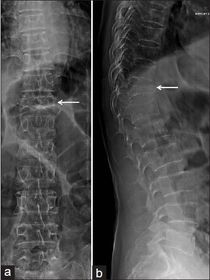

What is shown by the arrow? Typical osteoporotic # in the vertebrae (T11 in this eg).